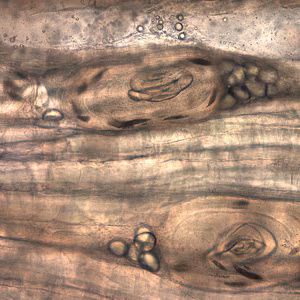

Larvae of Trichinella from bear meat.